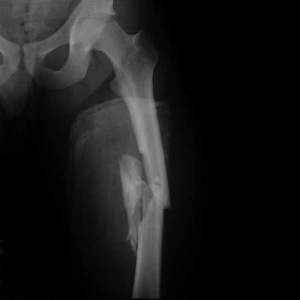

- Диафизарные переломы. Они возникают от непрямого и прямого механизма травмы. Уровень повреждения определяет его вид. Перелом верхней трети бедра из-за действия мышечной тяги приводит к тому, что кпереди смещается центральный отломок. Его смещение также происходит кнаружи. Периферический отломок подтянут кверху. В случае перелома средней трети центральный отломок немного отклонен кнаружи и кпереди, а периферический слегка приведен и смещен кверху. Конечность деформируется из-за сильного смещения и искривления. В случае перелома нижней трети центральный отломок смещается кнутри и кпереди из-за сильных приводящих мышц и тяги сгибателей. Короткий периферический отломок отклонен кзади. Костный фрагмент может повредить нервно-сосудистый пучок.

- Переломы дистального отдела или нижнего конца кости. Обычно это происходит из-за прямого удара по коленному суставу или падения. При этом может произойти перелом бедра со смещением. Возрастает количество переломов бедра у пожилых людей. Может произойти смещение одного или двух мыщелков. Смещение отломков происходит в строну и вверх. Кость из места повреждения выливается в сустав, что приводит к гемартрозу.